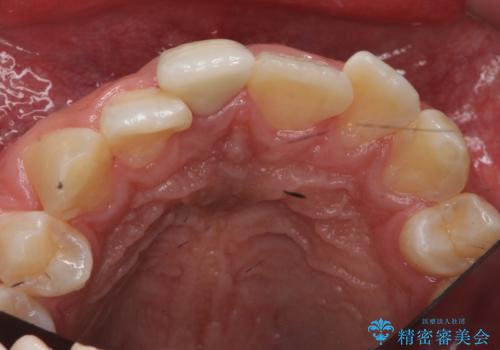

変色した前歯 根の治療とセラミックで白い歯に

- 前歯の変色を主訴に来院。

神経が死んでいたため、神経の治療を行いました。

また、全体的に歯石がついており、歯ぐきから出血しやすい状態であったため、TBI(歯磨き練習)を行い、歯茎の炎症をしっかり収めてから治療しました。

- 24.2万円 内訳:セラミッククラウン(ジルコニアクラウン、スペシャル)14.3万円、精密根管治療(前歯、イニシャル)6.6万円、仮歯1.1万円、ファイバーコア2.2万円費用は治療当時の料金となります

今後矯正治療をするかもしれない(未定)とのことでした。

その際、支障がでないように、患者様と相談し、他の歯を削って並びを整えるようなことはせず、前歯の角度はそれなりにそろえる形にしました。